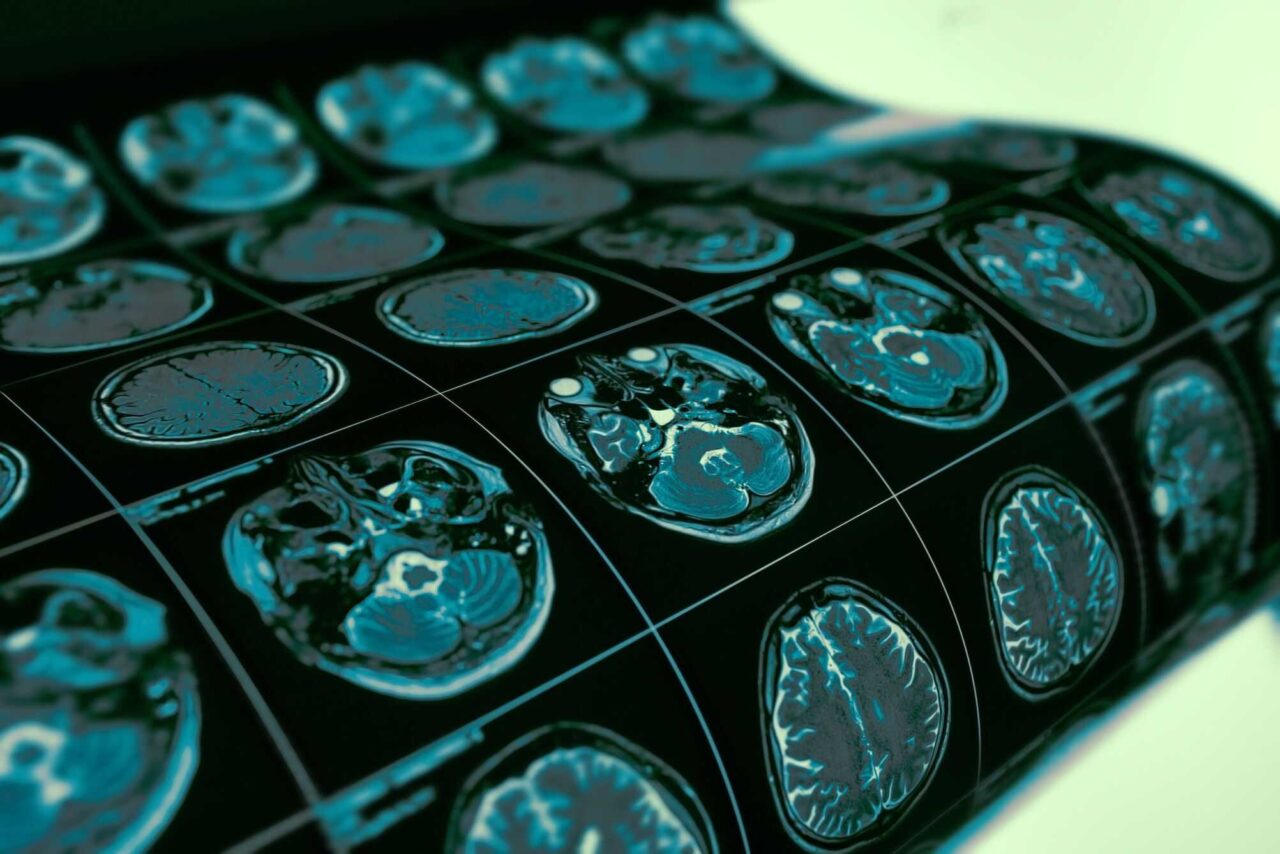

- Para medir essa reorganização, os cientistas utilizaram redes baseadas na chamada Divergência Inversa Morfométrica (MIND, na sigla em inglês), que avaliam o grau de similaridade morfológica entre diferentes regiões a partir de imagens de ressonância magnética. Valores menores de MIND indicam maior desconexão estrutural.

A equipe analisou redes MIND de 195 indivíduos neurotípicos e 352 pessoas com TEE. O grupo com a condição apresentou as maiores quedas na similaridade estrutural justamente em áreas associativas de ordem superior — que amadurecem mais tarde e são cruciais para funções cognitivas complexas. As reduções foram mais fortes em pacientes com pior quadro clínico.